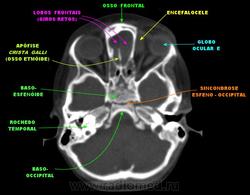

Орбитальная патология. Черепно-мозговые грыжи. +

Фронто-орбитальное энцефалоцеле